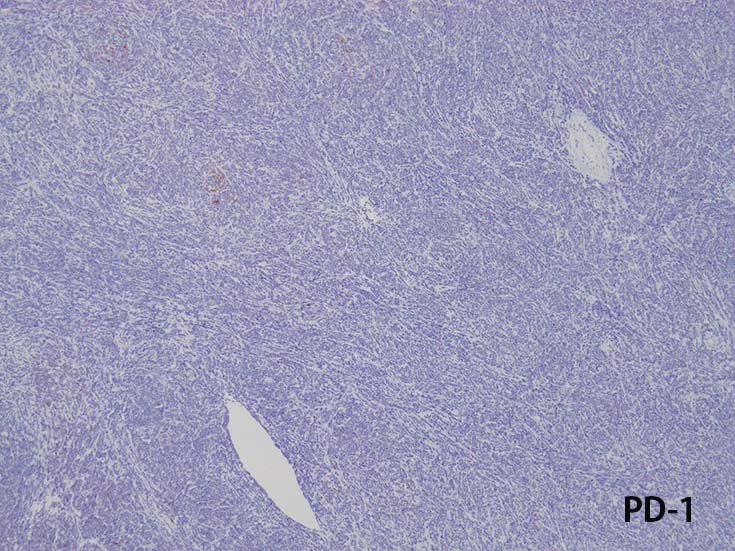

Immunophenotype of T-ALL/ LBL

- TdT, CD34に加えて, CD99と CD1a陽性はT-lymphoblastsの前駆細胞の性質を確認するのに役立つ.

- CD1a, CD2, surface CD3 (dim), CD4, CD5, CD8は種々の程度に発現する.

- T-ALL はしばしば, CD4とCD8の double positive となる. またCD10が陽性になる

- CD4,CD8 double positiveはT-prolymphocytic leukaemiaでも認められる. CD10もPTCL(第一にはAITL)に陽性となることに注意.

- cytoplasmic CD3 のみがT-cell lineage特異的なマーカである.

- MPO, lysozymeは発現しない. CD13+, CD33+, CD13,CD33 both+ (19-32%). myeloid marker発現はT-ALL/LBLの診断を否定できない.

また,myeloid mraker発現があるからといって, T/myeloid mixed phenotype acute leukaemiaと診断してもいけない.

- まれにc-KIT(CD117)+; FLT3の活性化変異に関連する.